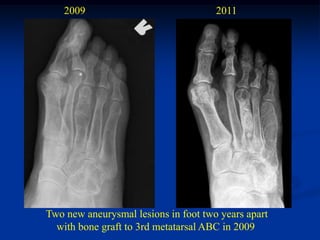

2009                              2011

Two new aneurysmal lesions in foot two years apart

with bone graft to 3rd metatarsal ABC in 2009